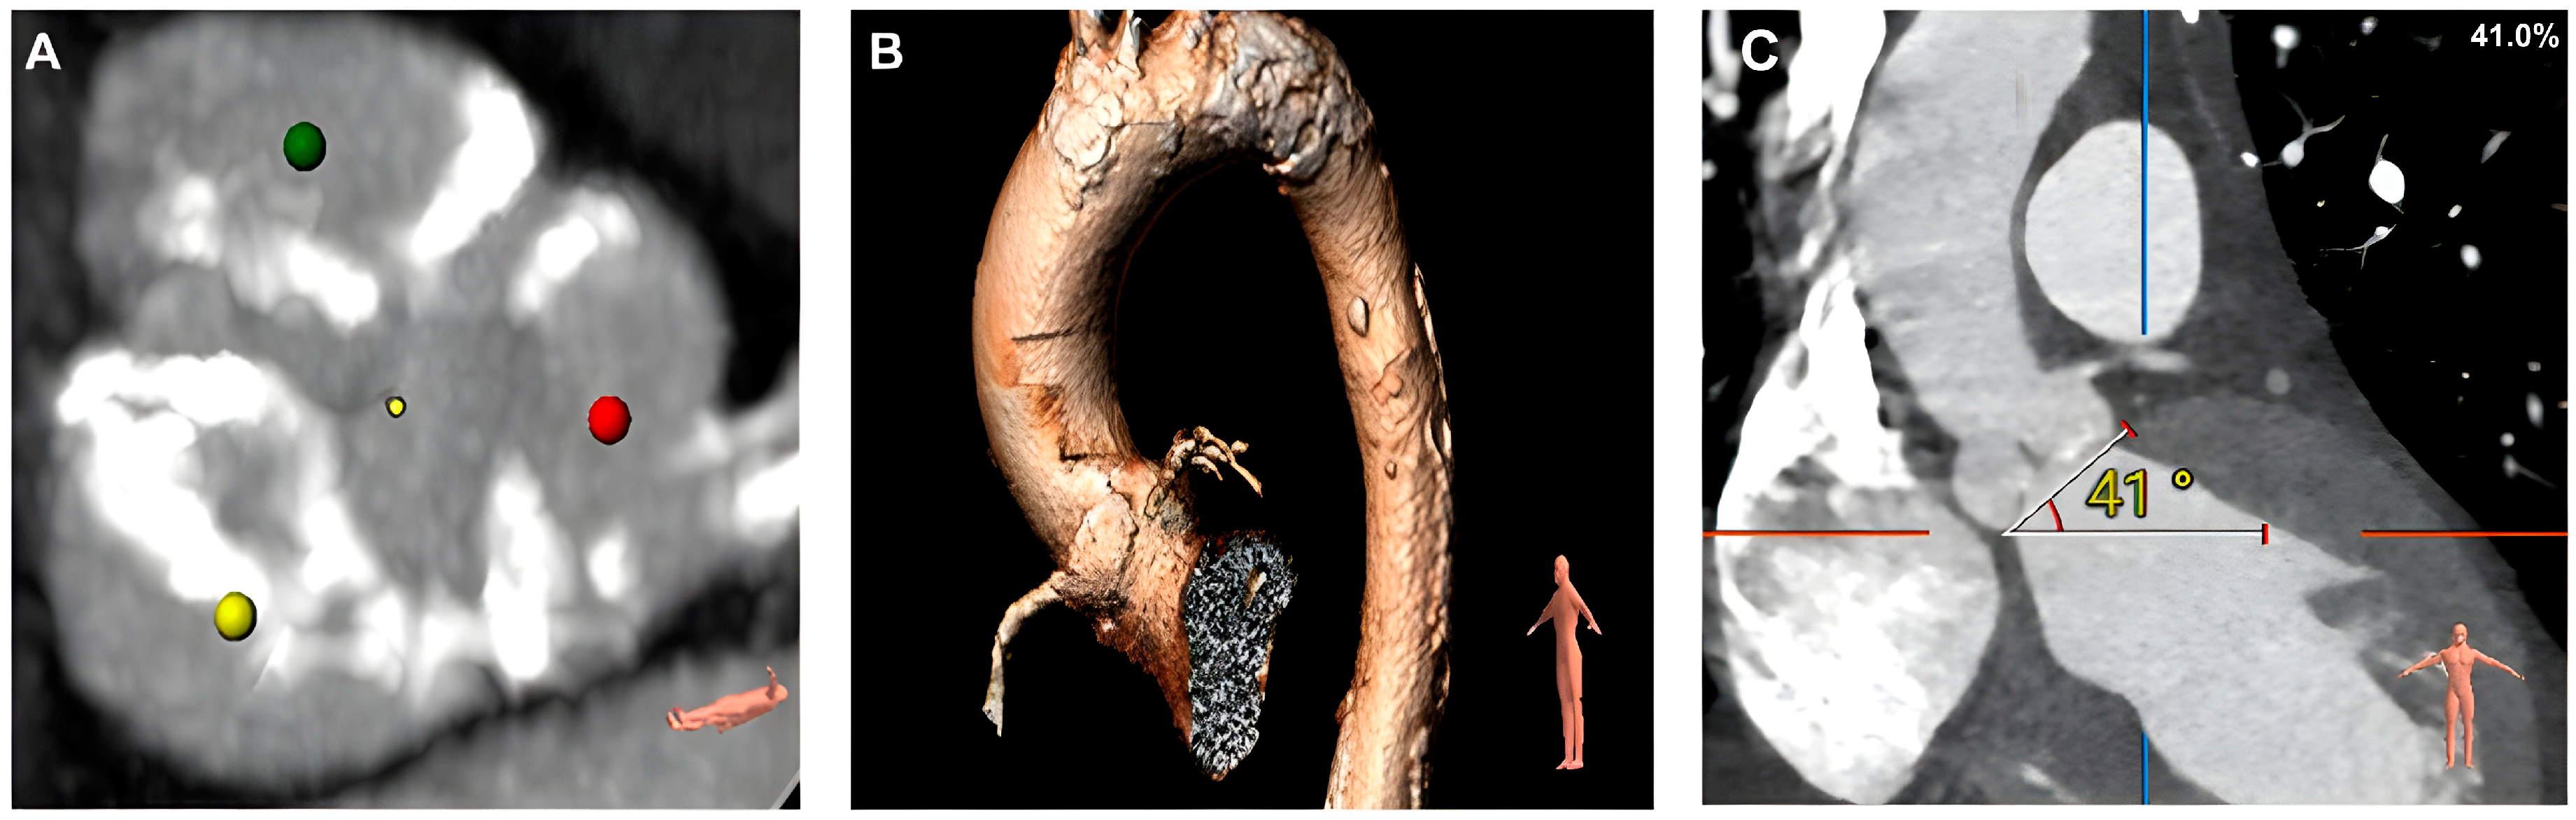

2. Case Presentation